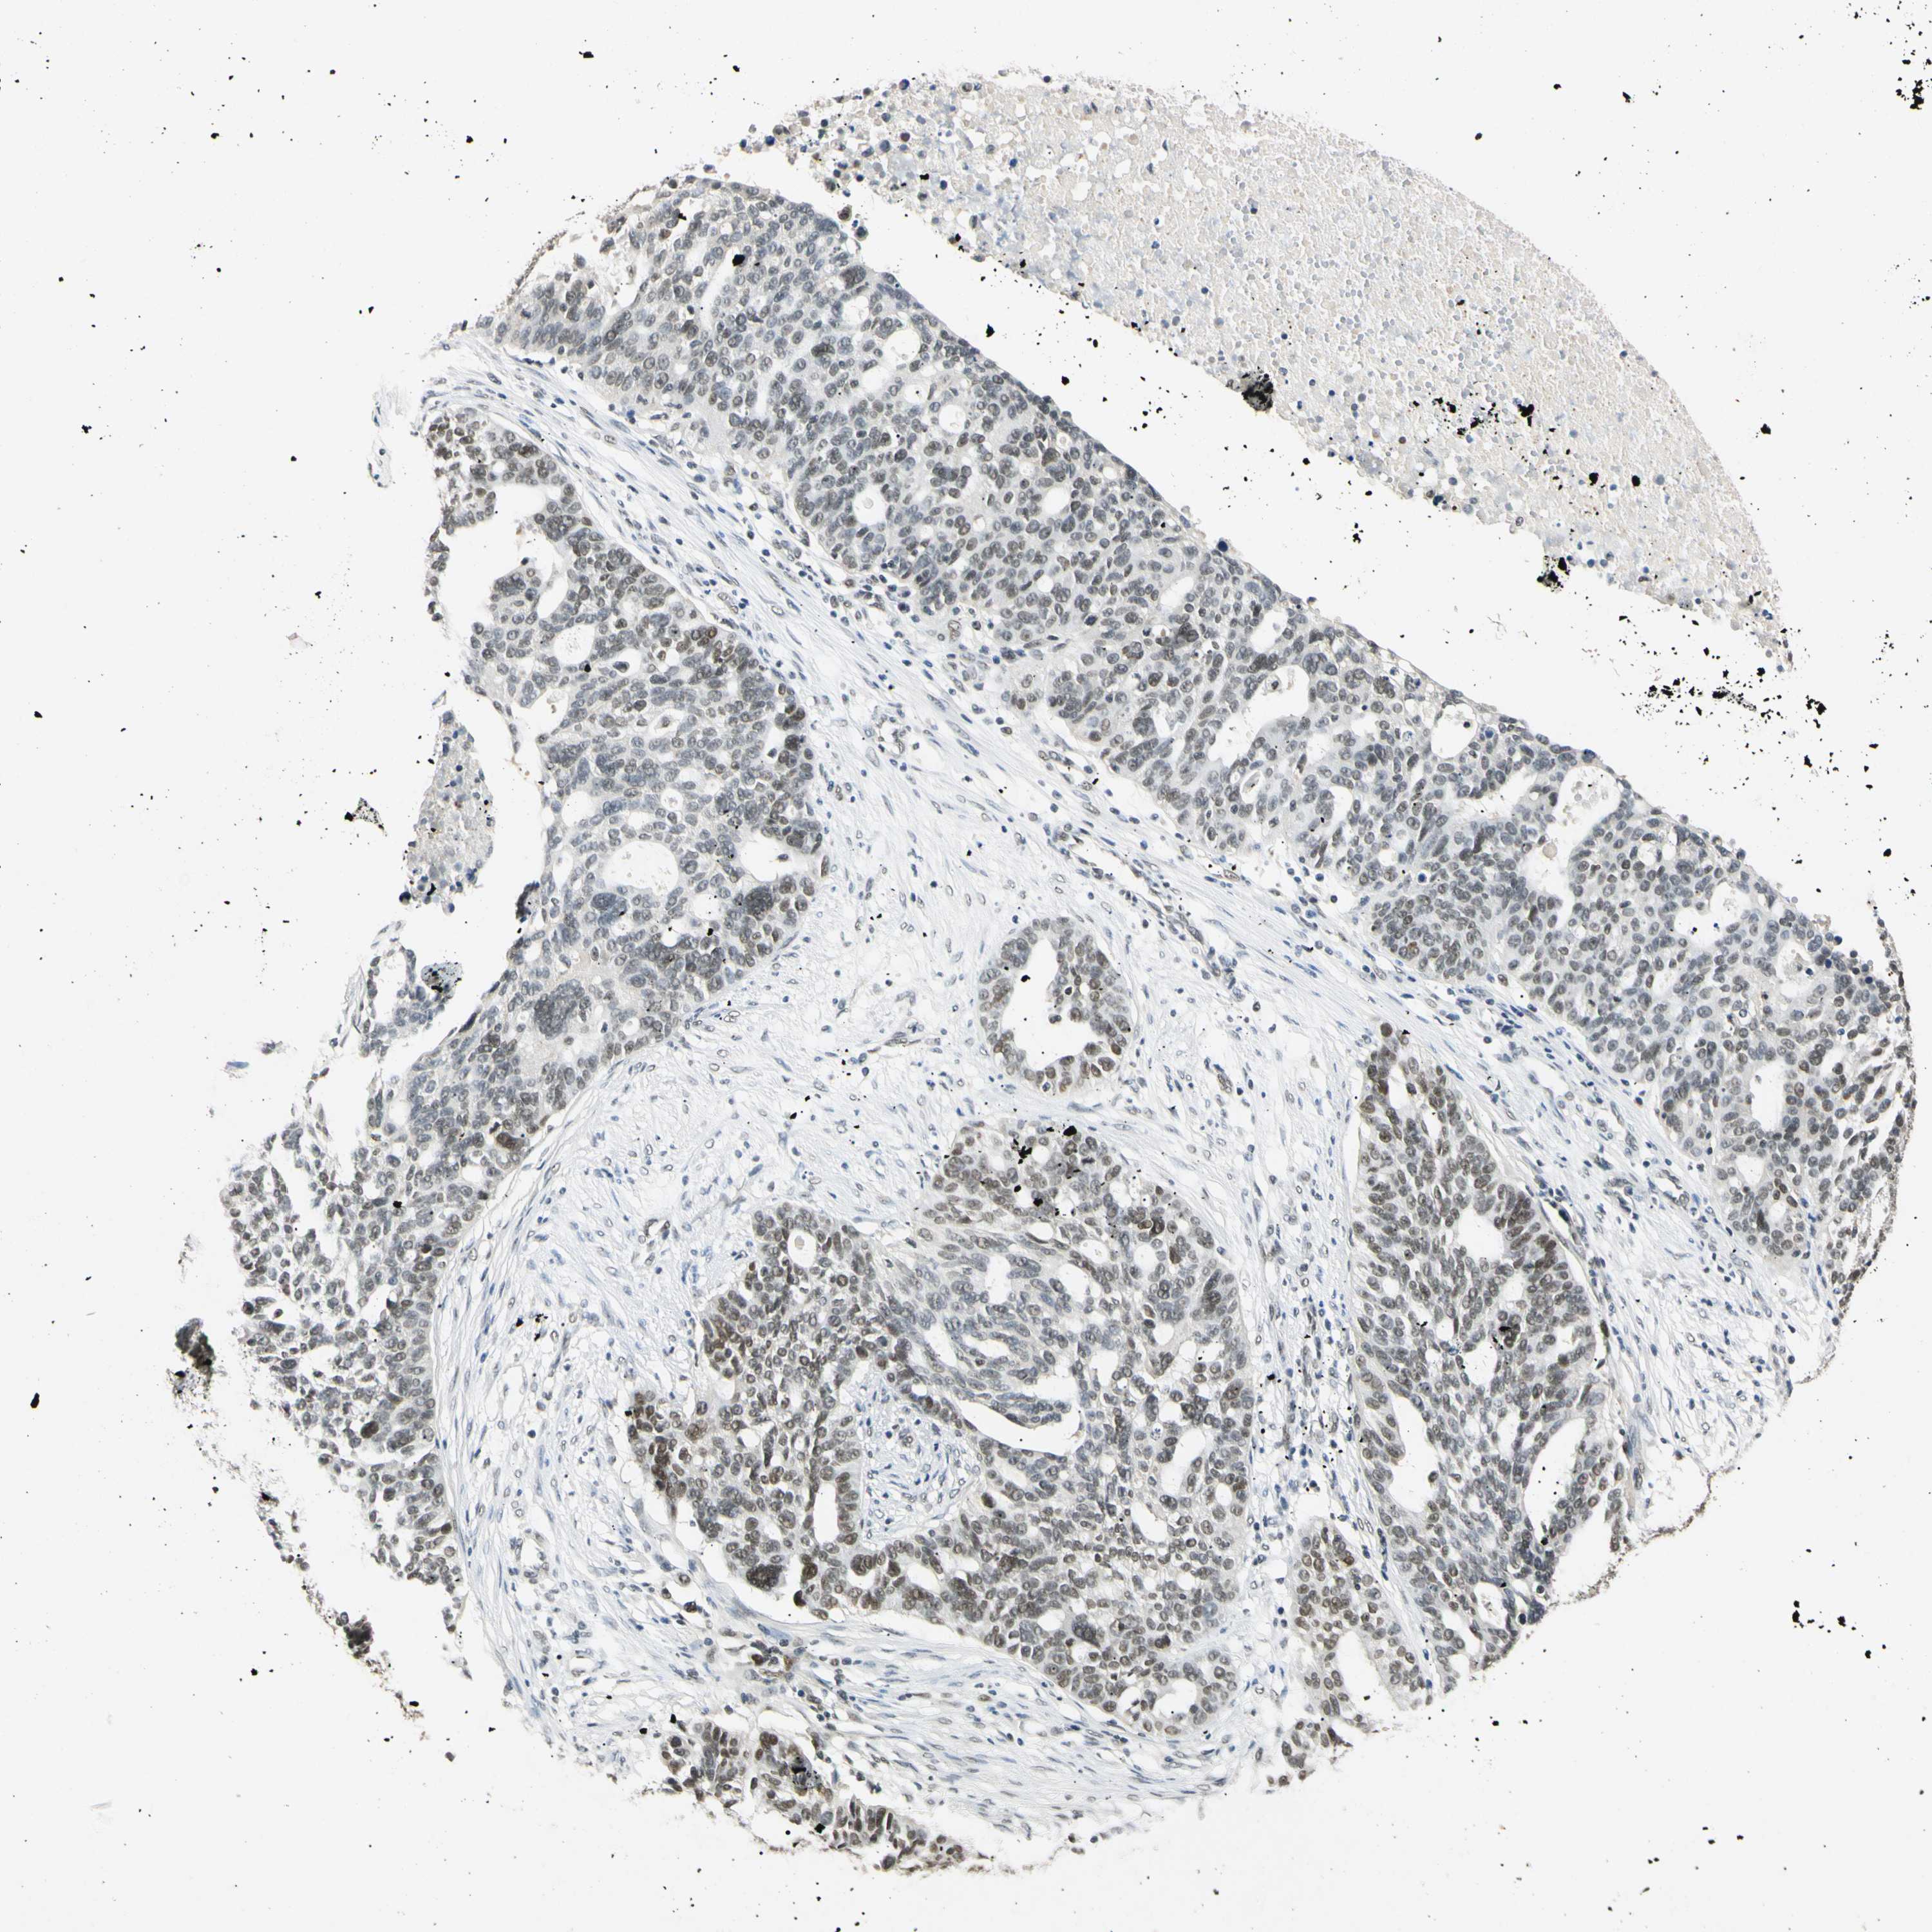

OVARIAN CANCER - Protein expressioni

A mouse-over function shows sample information and annotation data. Click on an image to view it in a full screen mode. Samples can be filtered based on level of antibody staining by selecting one or several of the following categories: high, medium, low and not detected. The assay and annotation is described here.

Note that samples used for immunohistochemistry by the Human Protein Atlas do not correspond to samples in the TCGA dataset.

Antibody stainingi

Antibody staining in the annotated cell types in the current human tissue is reported as not detected, low, medium, or high, based on conventional immunohistochemistry profiling in selected tissues. This score is based on the combination of the staining intensity and fraction of stained cells.

Each image is clickable and will lead to virtual microscopy that enables deeper exploration of all samples and also displays staining intensity scores, fraction scores and subcellular localization as well as patient and tissue information for each sample.

Antibody HPA008751

Antibody CAB005227

Cystadenocarcinoma, serous, NOS